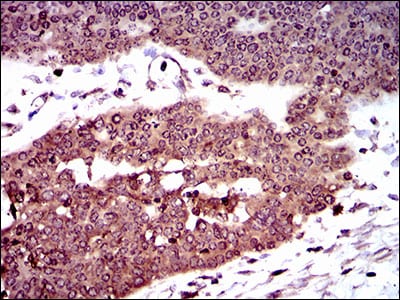

Immunohistochemical analysis of paraffin-embedded human cervical cancer tissues using DCTN4 mouse mAb with DAB staining.

Immunohistochemical analysis of paraffin-embedded human ovarian cancer tissues using DCTN4 mouse mAb with DAB staining.